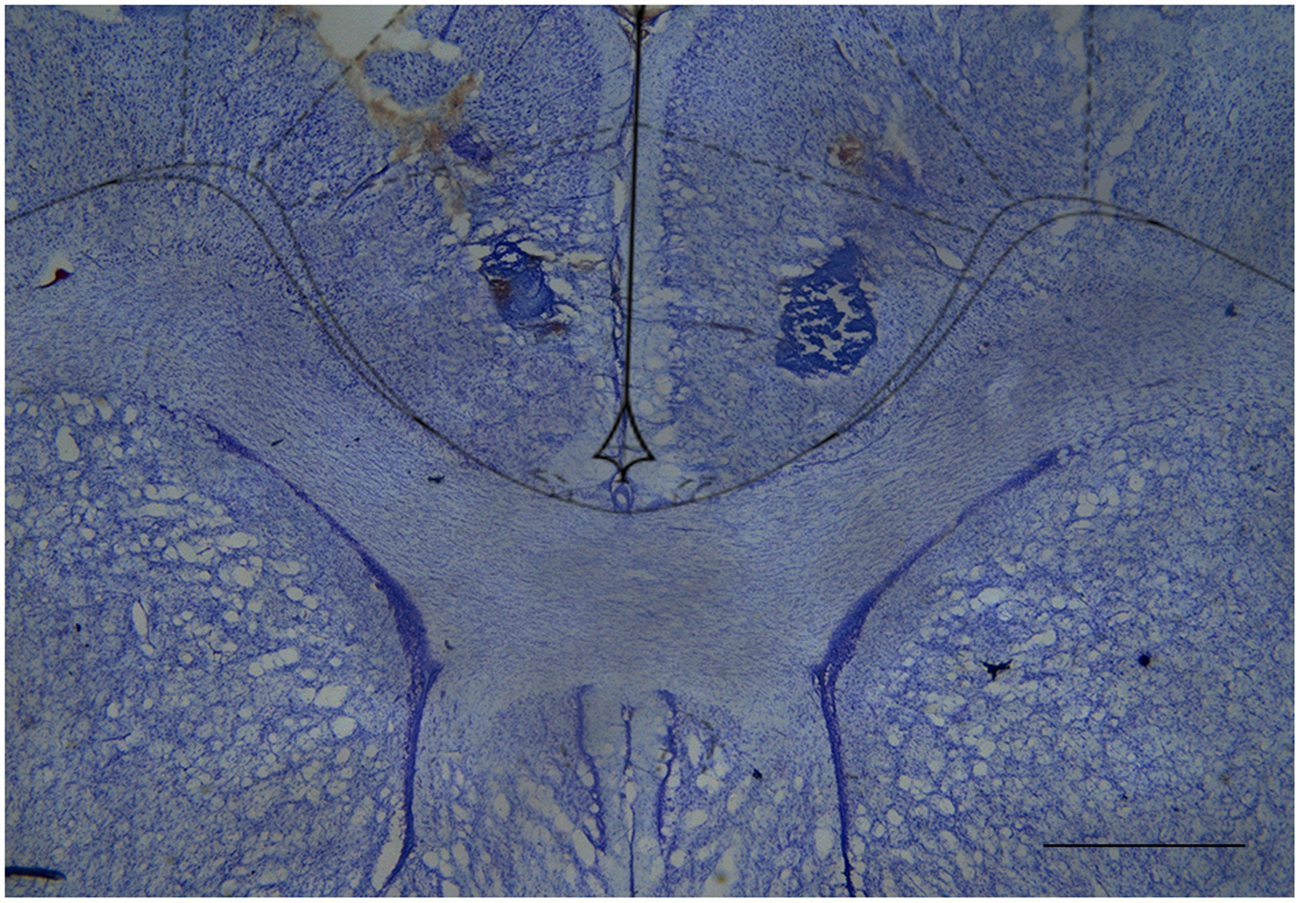

The great majority of injection sites were concentrated in the rACC (2.28 to 1.80 mm in relation to bregma). Representative photomicrograph of injection sites is shown in Figure 4. Time line of the protocol for the experiments is shown in Figure 5A. The local injection of CBD (40 nmol/0.25 μL) produced a reduction of the mechanical allodynia that lasted for at least 120 min. The decrease of mechanical allodynia started 20 min after CBD (10 and 40 nmol/0.25 μL) but was maximal at 90 min after the highest dose, which elicited a significant increase in the force required for paw withdrawal. The differences were statistically significant in terms of time [F(7.476) = 133.4; p < 0.01], treatment [F(5,68) = 134.1; p < 0.01] and interaction time × treatment [F(35,476) = 17.2; p < 0.01]. The threshold of the non-incised hind paw did not change throughout the period of observation (Figure 5B). Figure 5C illustrates the microinjection sites in the rACC on diagrams of cross-sections from the atlas of Paxinos and Watson (2006).

FIGURE 4

Cresyl violet-stained tissue showing the location of the cannula tip in the rostral anterior cingulate cortex. Scale bar = 1 mm.